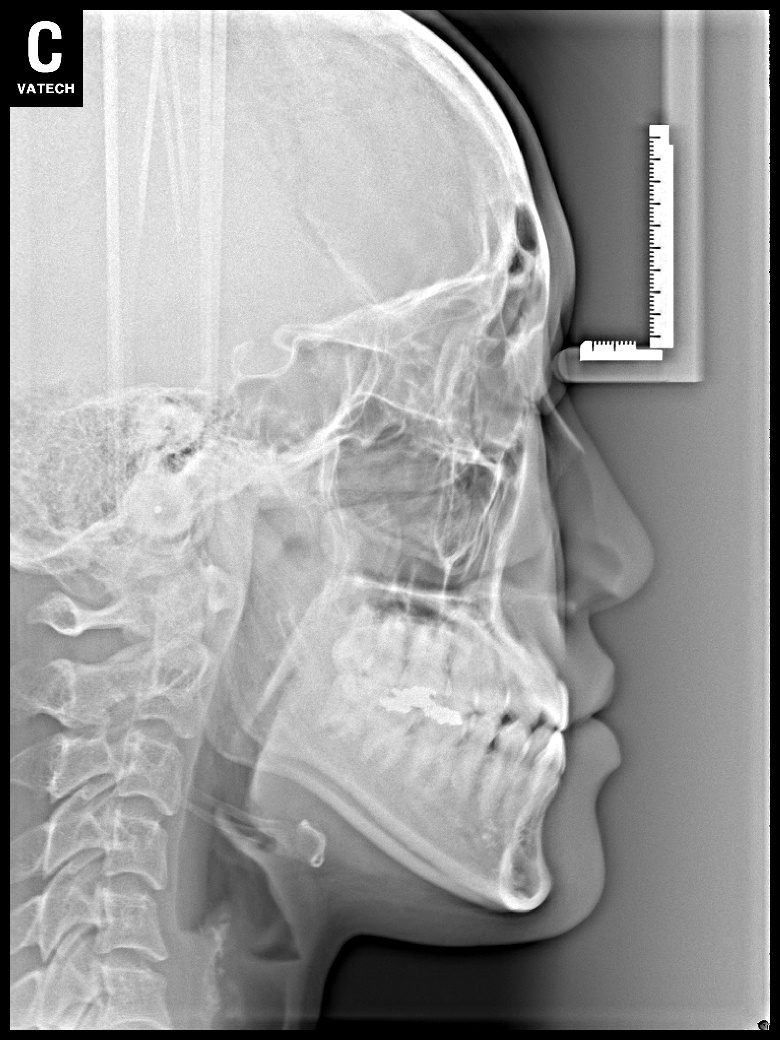

치료 전 사진입니다.